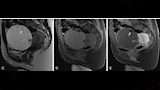

نجح فريق جراحة الأورام بمستشفى السنبلاوين العام بمحافظة الدقهلية، في إجراء عملية دقيقة لاستئصال كيس ضخم بالحوض لمريضة تبلغ من العمر 46 عامًا، كانت تعاني من آلام مزمنة، ووُصفت حالتها بالنادرة نظراً لتاريخها الطبي المعقد.

وقال الدكتور تامر مدكور، وكيل وزارة الصحة بالدقهلية: "إن المريضة حضرت إلى عيادة جراحة الأورام وهي تعاني من آلام مستمرة بالحوض، ولديها تاريخ مرضي يتضمن استئصالًا جزئيًا للرحم، بالإضافة إلى استئصال كيس سابق على المبيض. وبعد إجراء الفحوصات الطبية والأشعة، تبيّن وجود كيس حجمه 10 سم في منتصف الحوض".

وأوضح "مدكور" أنه فور التشخيص، تم تجهيز الحالة للعملية، وخضعت لجراحة استكشافية تم خلالها: فك الالتصاقات الناتجة عن العمليات السابقة، استئصال الكيس الحوضي، استئصال كيس آخر على المبيض، إلى جانب إصلاح فتق جراحي، وهي خطوات تطلبت تنسيقًا دقيقًا بين أعضاء الفريق الطبي.